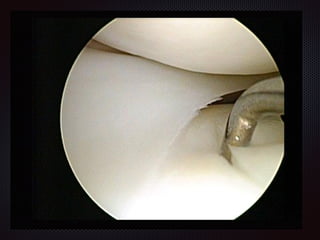

Figure 9.3 Structure of a typical synovial joint. Note the two layers of the articular capsule—the fibrous mem

the synovial membrane. Synovial fluid lubricates the joint cavity between the synovial membrane and

articular cartilage.

The distinguishing feature of a synovial joint is the synovial cavity between the articulating bone